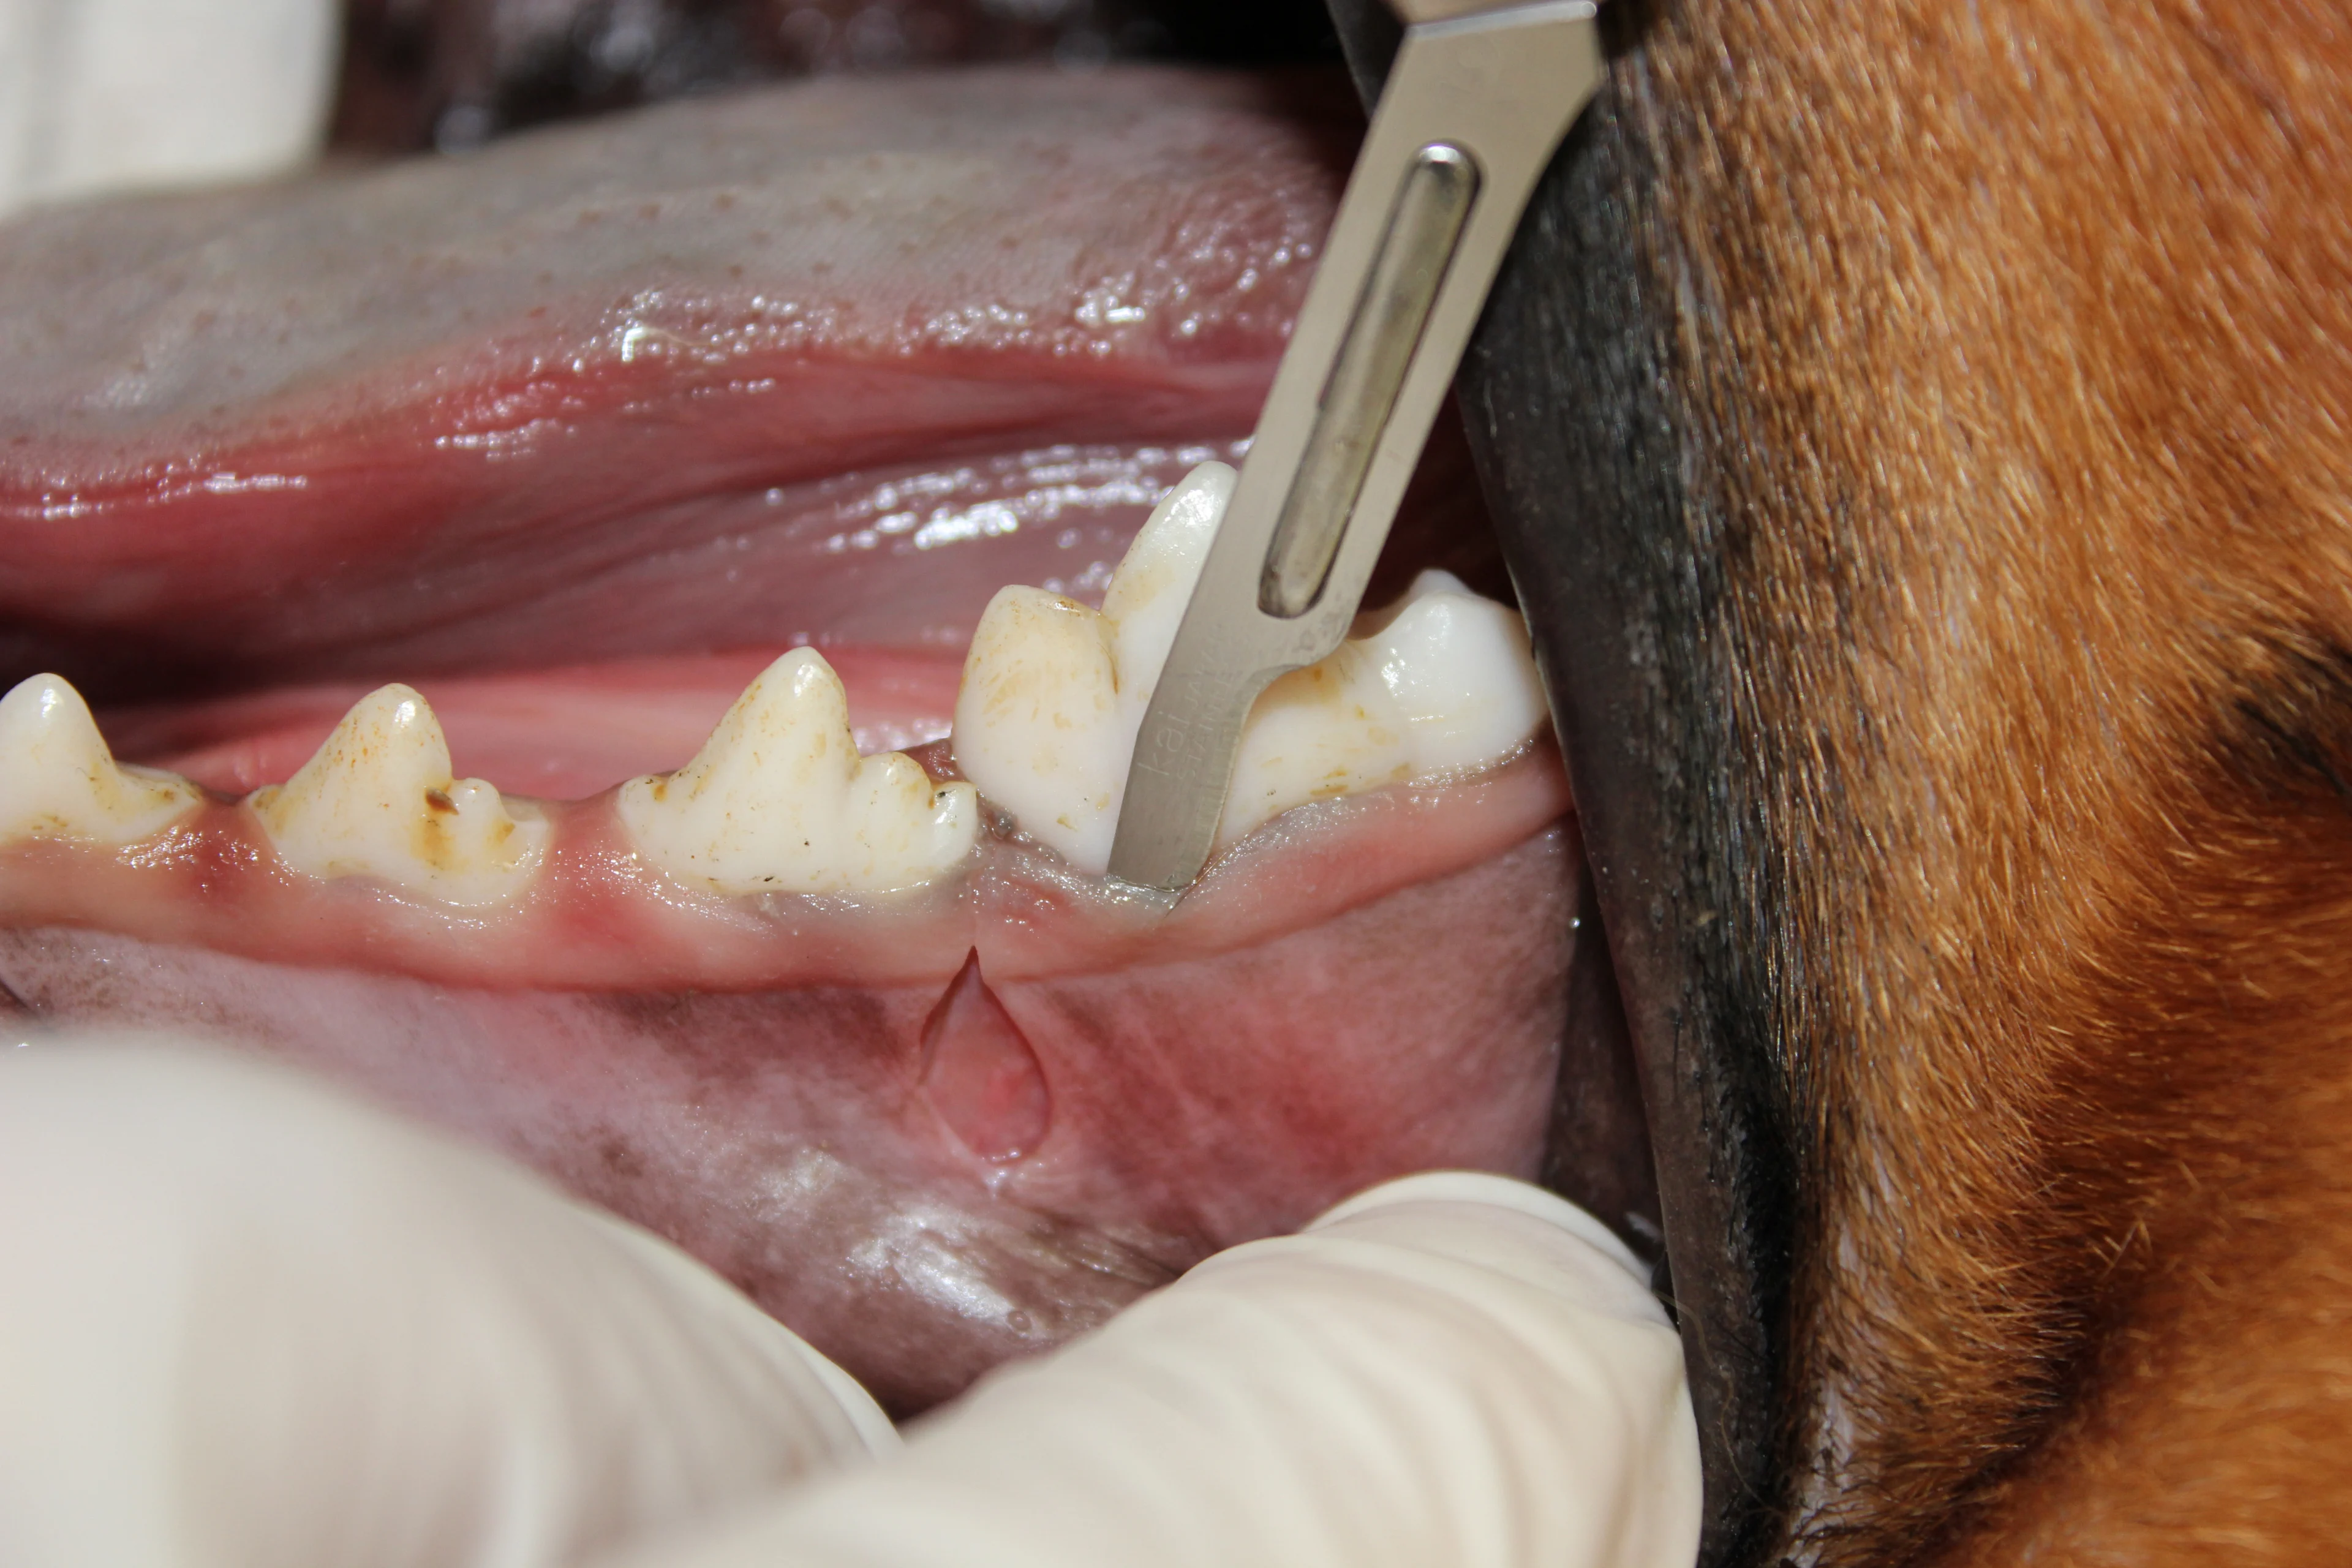

(A) Gently slide the periosteal elevator under the attached gingiva at the corner of the flap. Gently rotate and advance the elevator along the attached gingiva until all attached gingiva is freed. (B) Elevate the remaining alveolar mucosa with the same technique in an apical direction.

Use a #8 round bur in a water-cooled high-speed handpiece with light pressure to remove the alveolar bone and expose the furcation.